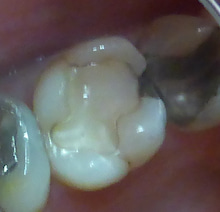

そこで、 歯に詰まっている

樹脂を外してみました。

歯はほとんど削っていません。

大きな穴が開いて 神経が見えそうです。

なんとなく、真ん中のところが茶色いですね。

とがったもので 触ると 神経に触れそうです。